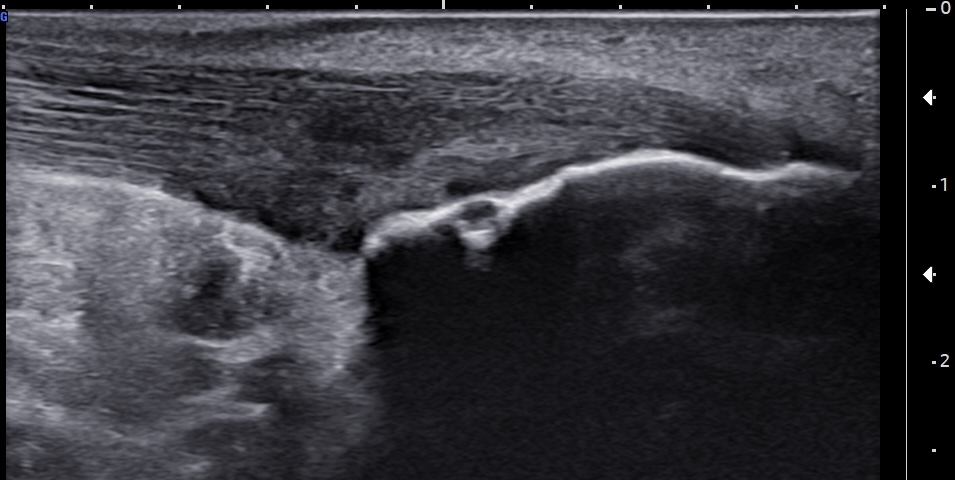

Unlabeled long-axis ultrasound image of the insertional and pre-insertional Achilles tendon using color Doppler, demonstrating a few neovessels at the retrocalcaneal bursa and within the deep tendon fibers, consistent with chronic bursitis and tendinopathy.